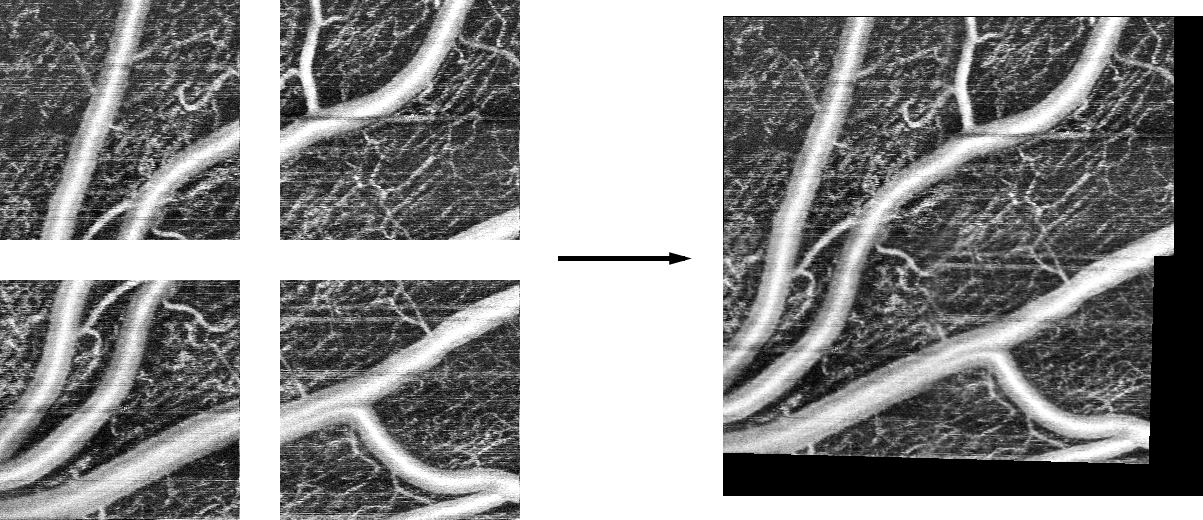

Thesis product is a program called mostitch that automatically stitches set of retinal angiography eye images. Below is an example set of input images and the output of mostitch program.